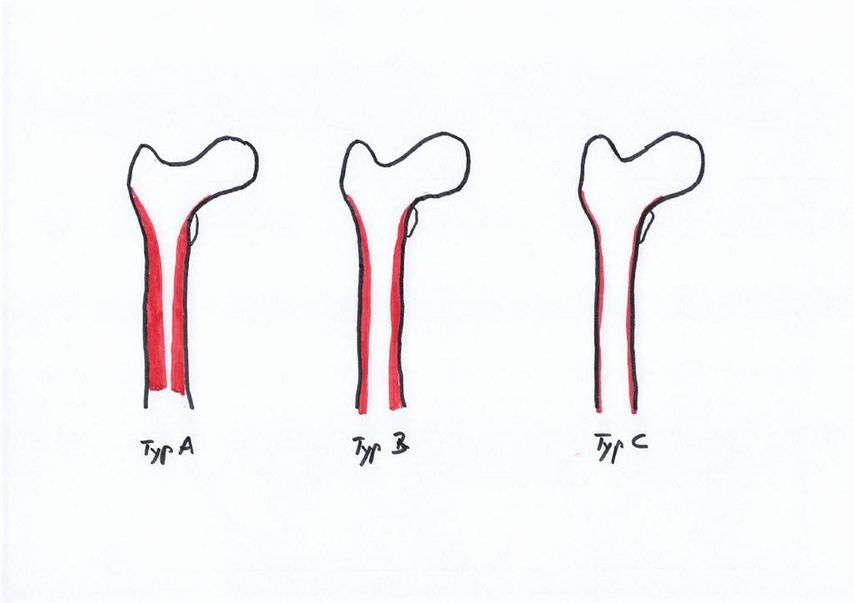

Dorr et al.17,18 entwickelten 1993 eine Einteilung in drei Femurtypen, um röntgenologisch eine Einschätzung der Knochenqualität zu ermöglichen (Abb.1). Der Dorr-Typ A zeigt einen schmalen Diaphysenkanal und wird auch als «Champagnerflöte» bezeichnet. Dieser Typ wird häufiger bei jüngeren, schwereren und männlichen Patienten beobachtet. Der Typ B ist durch eine Reduzierung der medialen und dorsalen Kortikalis gekennzeichnet, was zu einer Verbreiterung des Diaphysenkanals führt. Dieser Femurtyp kommt häufiger bei Männern als bei Frauen vor. Der Dorr-Typ C wird auch als «Ofenrohr» bezeichnet und ist durch einen breiten Kanaldurchmesser charakterisiert, der häufiger bei dünneren, älteren weiblichen Patienten auftritt. Die Inzidenz periprothetischer Frakturen ist bei Patienten mit Dorr-Typ C deutlich erhöht. Gkagkalis et al.19 stellten im Rahmen einer Multicenterstudie fest, dass bei Implantation einer Kurzschaftprothese und Vorliegen eines Dorr-Typs C die Inzidenz einer periprothetischen Fraktur um über 20% erhöht ist.